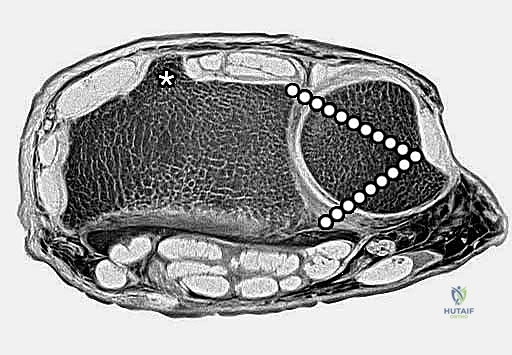

تعد الكعبرة البعيدة بمثابة الدعامة الأساسية الحاملة للوزن في الرسغ، حيث تنقل ما يقدر بنحو 75% إلى 80% من الحمل المحوري من اليد إلى الساعد. أما نسبة الـ 20% إلى 25% المتبقية، فتحملها الزند البعيد والمثلث الغضروفي الليفي (TFCC).

لذلك، فإن أي تغيير، ولو كان طفيفًا، في تشريح الكعبرة البعيدة يؤثر بشكل عميق على ميكانيكا الرسغ، مما قد يؤدي على المدى الطويل إلى تآكل الغضاريف، الألم المزمن، وتطور الفصال العظمي (الخشونة المبكرة). يتكون السطح المفصلي للكعبرة من انحناءات دقيقة تتناسب مع عظام الرسغ (العظم القاربي والهلالي)، ويجب استعادة هذا السطح بدقة متناهية لتجنب المضاعفات المستقبلية.

يقوم الدكتور هطيف بعمل شق جراحي دقيق (طوله حوالي 5-8 سم) على الوجه الأمامي للرسغ، عادة على طول مسار وتر العضلة المثنية الكعبرية للرسغ (FCR). يتم إبعاد الأوتار والأعصاب (خاصة العصب الأوسط) بلطف شديد لحمايتها.